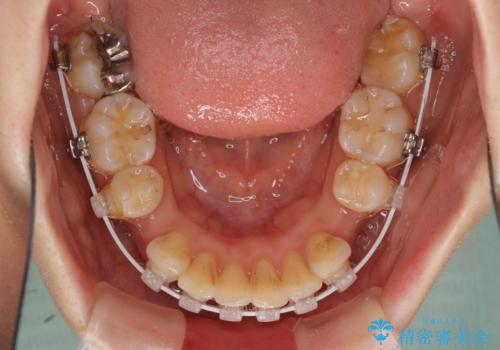

- 審美装置

- 上下の出っ歯を気にして来院された患者様です。

口元を積極的に引っ込めるために、上下左右の第一小臼歯を4本抜歯することとしました。

元々ディープバイトのため、スペースを閉じている期間に上下前歯が接触してしまい、治療期間が想定よりも伸びてしまいました。